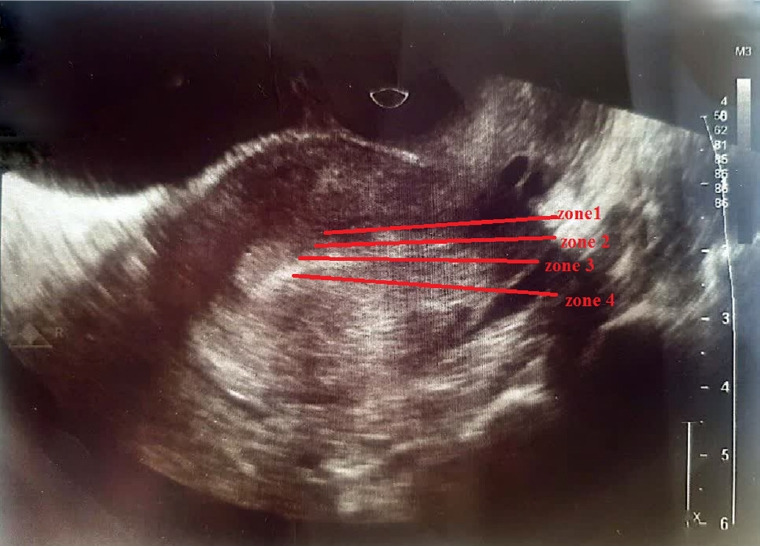

Methods: Between February and November 2023, our reproductive facility conducted a single-center randomized clinical trial, enrolling 100 patients with previous implantation failure and at least one uterine PI measurement exceeding 3. Participants were randomly assigned to receive either amlodipine (5 mg) or placebo (n=50 per group). Hormone replacement therapy was the predominant method for endometrial preparation. Transvaginal ultrasonography was used to measure uterine artery resistance and pulsatility on day 1 or 2 of menstruation. Women in the amlodipine group received 5 mg nightly. Following repeat transvaginal ultrasound to assess PI and RI, ET was performed. If a positive pregnancy test was obtained, treatment continued for a total of 7 weeks.